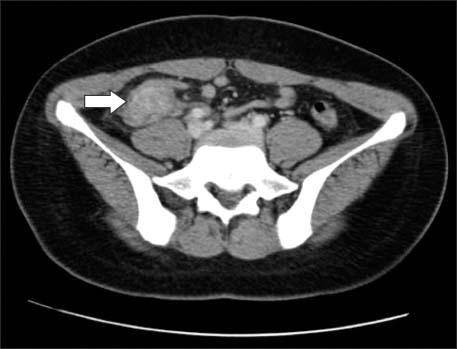

Operative findings showed a 3×3 cm appendiceal mass with dense severe adhesions (Fig. 2A, B) for which we performed an ileocecectomy.

Fig. 2

Intraoperative findings. (A) Laparoscopic appearance of appendiceal actinomycosis. (B) Gross appearance of appendiceal actinomycosis; a 7.0×4.0 cm appendiceal mass. Severe inflammation and adhesion between the appendix and the adjacent appendiceal serosal surface is visible.

Fig. 2 Intraoperative findings. (A) Laparoscopic appearance of appendiceal actinomycosis. (B) Gross appearance of appendiceal actinomycosis; a 7.0×4.0 cm appendiceal mass. Severe inflammation and adhesion between the appendix and the adjacent appendiceal serosal surface is visible.